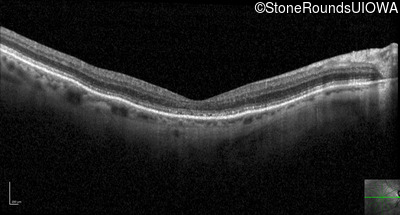

Optical Coherence Tomography - Left - 20/400

Exemplar / OCT Stack

OCT Stack